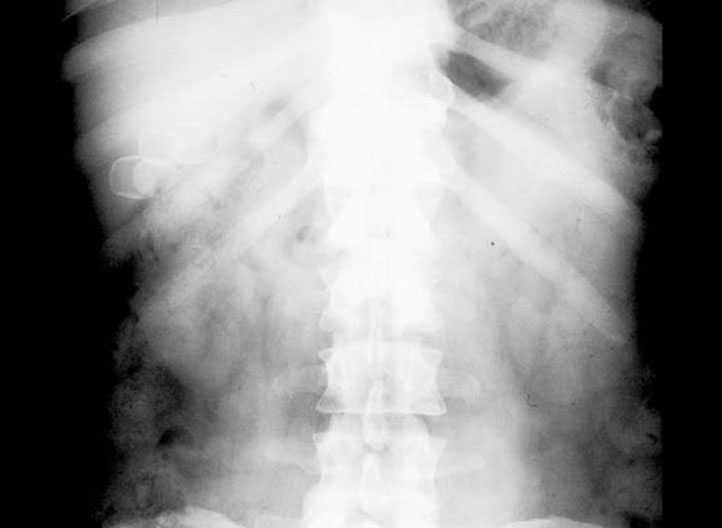

1. Gallstones